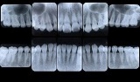

歯周病の精密検査

歯周病は高血圧などと同様な慢性疾患です。現在の歯周病の進行状態を詳しく把握し、適切な治療を行うことはもちろんですが、どうして歯周病が発症・進行してしまったのかという原因を把握してその原因を除去することがとても重要になり、これを行わないと治癒したはずの歯周病がまた再発してしまいます。

T&T歯科・矯正歯科クリニックでは、精密検査の結果をわかりやすく説明し、歯の保存に最善を尽くします。